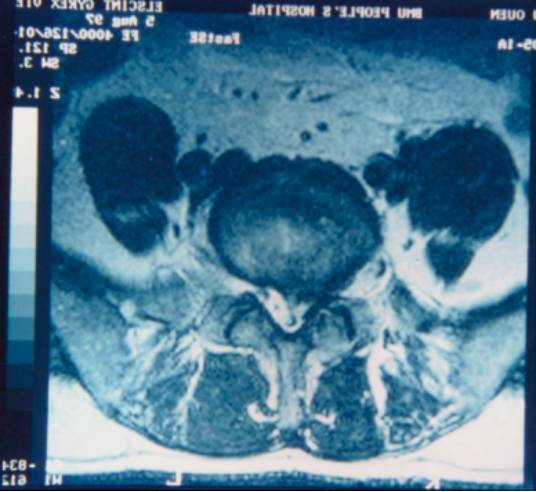

5、MRI检查:此检查能进行横断面、矢状面、斜切面的扫描。软组织显示好,尤其对髓内病变诊断率高。

椎管狭窄硬膜囊受压

神经根管狭窄